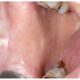

El almacenamiento prolongado de hierro ocurre principalmente en los hepatocitos, las células del hígado. Aquí, el hierro se almacena en dos formas: como ferritina, una forma soluble y segura, y como gránulos de hemosiderina, que se forman cuando los niveles de hierro son elevados y la ferritina se satura. Este proceso proporciona una manera eficaz de regular los niveles de hierro en la sangre, liberándolo o almacenándolo según las demandas fisiológicas del organismo.

Estudios recientes respaldan la importancia de los hepatocitos como los sitios principales de almacenamiento prolongado de hierro. Esta función hepática es esencial para mantener el equilibrio de hierro en el organismo, evitando tanto la deficiencia como la toxicidad. Los hepatocitos actúan como centros estratégicos que contribuyen a la gestión precisa del hierro, asegurando su disponibilidad cuando se requiere y previniendo desequilibrios que podrían afectar adversamente la salud general del organismo.